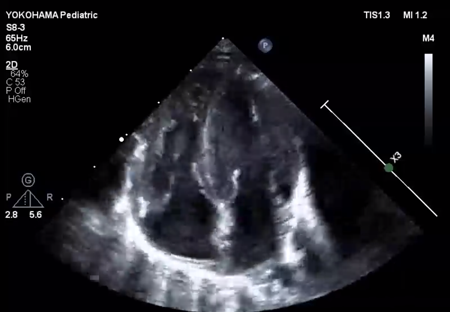

LV ejection fraction was down to 40% with moderate mitral regurgitation, whereas RV contractility was preserved. The biventricular volumes seemed well-balanced, and the LV end-diastolic diameter (15.9 mm) was within the normal range. Systolic RV pressure was estimated as 70 mmHg by regurgitation flow across the tricuspid valve (velocity 4.1 m/s), indicating persistent pulmonary hypertension. The ductus arteriosus had already closed. The foramen ovale (FO) was patent with very little blood flow through (Fig. 1A). The left atrium (LA) was dilated and non-contractile (Fig. 1B, Supplementary Video S1). Echocardiography showed a highly echogenic mass measuring 10×5 mm in the LA appendage, which was not mobile. The mass was suspected to be a thrombus (Fig. 1C, Supplementary Video S2). Blood tests indicated a high B-type natriuretic peptide (BNP) level (1,102.8 pg/mL) and a mildly elevated D-dimer level (2.27 µg/mL). There was no decrease in platelet count (279×103 /µL) or increase in clotting time (prothrombin time/international normalized ratio: 1.05, activated partial thromboplastin clotting time [APTT]: 29.9 s). The levels of fibrinogen (326 mg/dL), antithrombin-III (65%), protein C (35%), and protein S (68%) were within normal limits for neonates. There was no maternal history of systemic lupus erythematosus or antiphospholipid antibody syndrome, which could have affected neonatal formation of intracardiac thrombi.

Fig. 1 Echocardiographic findings

(A) Echocardiography at the time of admission (subcostal view) showed only a small slit-like blood flow across the foramen ovale. (B) Echocardiography on admission (four-chamber view) showed a dilated left atrium with an end-systolic volume of 4.0 mL. The left ventricular end-diastolic diameter was normal (15.9 mm). The left ventricular contraction was mildly reduced, with an ejection fraction of 40%. (C) Echocardiography on admission (short axis view) showed a highly echogenic and non-mobile mass (white *) of 10 mm ×5 mm in the left atrial appendage. (D) Echocardiography on day 9 showed improvement in left ventricular contractility. Atrial size had become normal, with a left atrial end-systolic volume of 2.1 mL. LA, left atrium; RA, right atrium.

We administered diuretics as well as continuous infusion of olprinone and unfractionated heparin. Continuous infusion of heparin was started at 10 U/kg/hr and gradually increased to 20 U/kg/hr, but the APTT was only slightly prolonged to 36.0 seconds on day 9. Daily echocardiography showed gradual improvement in LV function. Olprinone and diuretics were discontinued by day 9, because the LV ejection fraction improved to 65% and the LA size normalized (Fig. 1D, Supplementary Video S3). Marked mobility of the mass appeared in parallel with the restoration of LA contractility on day 10 (Supplementary Video S4). We performed a surgical thrombectomy on cardiopulmonary bypass so as to avoid systemic embolism. A white structure adhering to the LA appendage was excised (Fig. 2A), and pathological diagnosis was a calcified thrombus (Fig. 2B). The postoperative course was uneventful. Low-dose aspirin was started on the 3rd postoperative day. The patient was followed up on an outpatient basis, and aspirin was discontinued at 4 months postoperatively. At the time of this publication, the patient is 2 years old, and she has experienced no recurrent clots or embolic episode thus far.